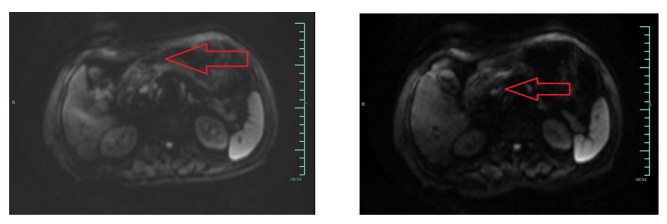

2)行胃平扫弥散+增强MRI(图4)示:病灶累及范围约5.6 cm;Borrmann分型:Ⅲ型(溃疡浸润型);浸润深度:累及浆膜下层;区域及远处淋巴结转移:有,胃小弯侧及胃窦部周围见多发稍大淋巴结影,DWI为高信号,强化不均。

图4 新辅助2周期后胃平扫弥散+增强MRI